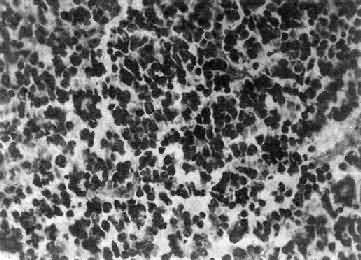

镜下,瘤细胞大小形态一致,呈梭形或胡萝卜形,胞核圆或椭圆,染色质呈细颗粒状,核膜清楚,有核仁。瘤细胞胞浆丰富,突起明显。瘤细胞的排列有二种特征,一是环绕空腔排列成腺管状,形态上与室管膜腔相似,称为菊形团形成,另一是环绕血管形成假菊形团结构,瘤细胞有细长的胞浆突起与血管壁相连(图16-25)。细胞中有神经胶质纤维,以PTAH染色在个别细胞的腔面或胞核旁可见纤毛体,后者与纤毛运动有关,是室管膜细胞的特征性结构。此外,有时还可形成乳头状结构。发生在脊髓圆锥和终丝的肿瘤,乳头状结构轴心中的结缔组织往往富含粘液。

图16-25 室管膜瘤

瘤细胞为圆形或卵圆形,核染色质丰富,胞浆少,可见有细长的胞浆突起与血管相连,呈放射关,形成假菊形团